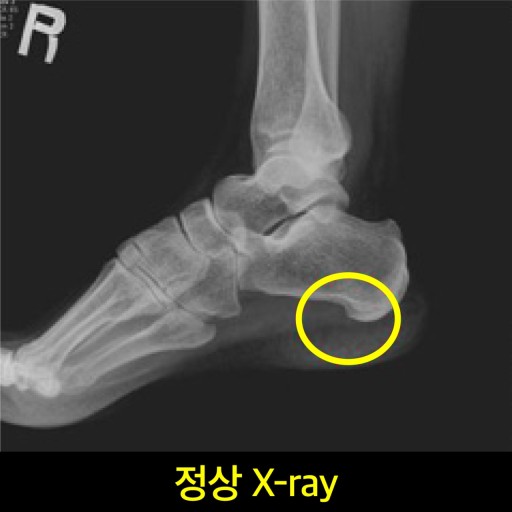

족저 근막염 증상 2. 발뒤꿈치 중앙 통증

- 발뒤꿈치 중간 또는 안쪽이 찌릿하거나 쑤시는 듯한 통증

- 눌렀을 때 통증이 더 심해지는 경우 많음